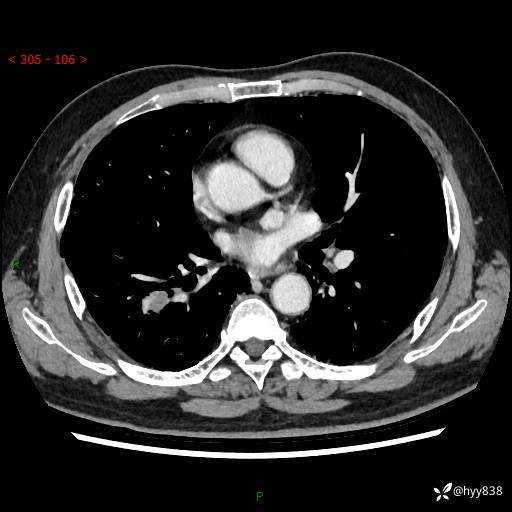

71岁/男,咳嗽伴气促半月。一年前肺手术史,又见两个结节,穿刺结果意外---结果公布~

【现病史】:患者半月前无明显诱因出现咳嗽、咳痰,为白色粘痰,无明显加重与缓解因素,伴气促,无发热,无大量脓痰,无胸痛、咯血,无哮鸣音,到我院就诊,胸部CT示右肺结节增大,并口服药物治疗无明显好转,具体用药不详,为求进一步治疗随来我院,经门诊以“孤立性肺结节”收入我科。 病程中患者精神、饮食可,睡眠不佳,大小便正常,体力下降,体重未见明显下降。

[既往史]:2022-06于当地第一人民医院确诊慢阻肺,现规律使用杰润(1次/日);2023-04-06于当地市第一人民医院行胸腔镜右肺上叶楔形切除术+右肺上叶切除术+淋巴结清扫术+胸膜黏连松解术,确诊为右肺鳞癌 pT2aN0M0 Ib期

【检查】:胸部CT平扫+增强